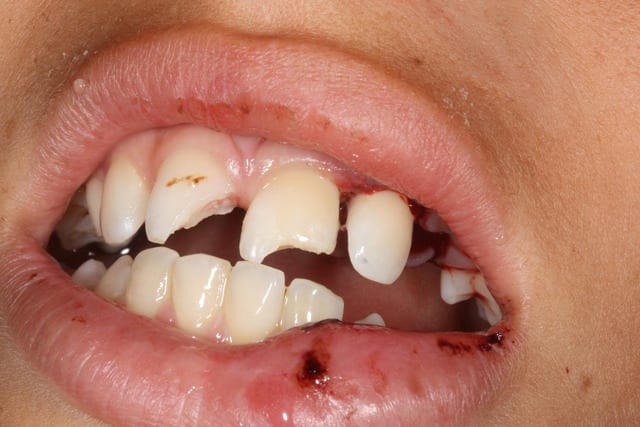

Historique: hier soir 18H coup de fil chez moi du parent d'un enfant de 12 ans, mon fils s'est cassé 3 dents en chutant. Donc je lui donne rendez vous ce matin.

Bilan: 11 21 fracturées mais la 22 est semi expulsée, collée à la gencive. Je me dis que je vais faire une réimplantation mais je découvre, en la prélevant, qu'elle a été fracturée . Reste donc la moitié de la racine que j'arrive à extraire avec une curette en laissant l'os et la racine intacte. J'ai traité le canal et recollé les deux morceaux et réimplanté.

Vous pensez que j'ai fait un truc inutile ou que le gamin a une chance?